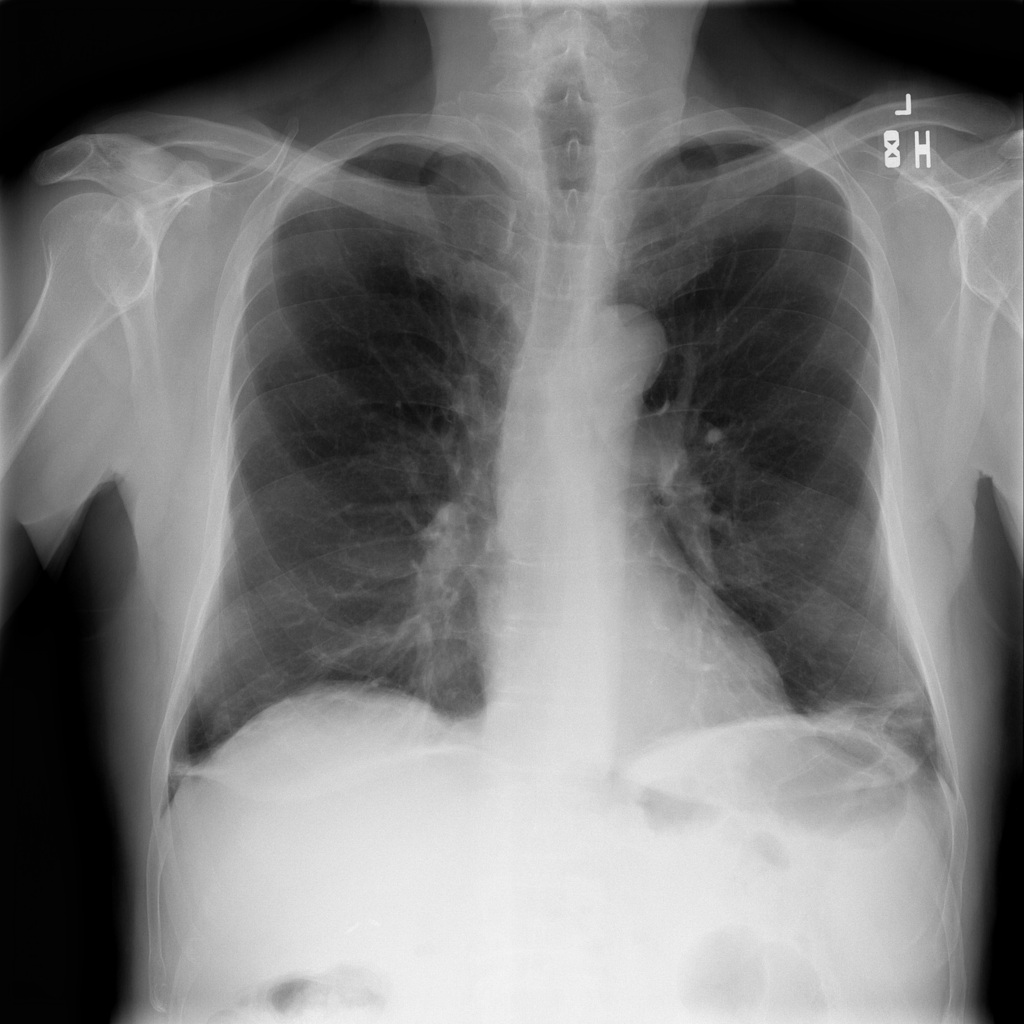

PAT-86C8 · IMG-006Atelectasis

PAT-86C8 · IMG-006

PA